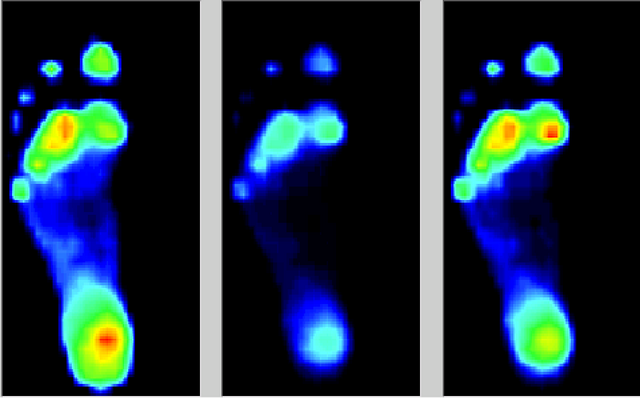

图为成人与儿童足底各点位压力:蓝色为成人,绿色为儿童

我们的脚与地面接触时,通常有三种模式:左图可见外侧用力偏多,这就是我们常说的“足内翻”,中间图压力比较均衡,右图内侧受力偏多,即“足外翻”。左图与右图中,在前足中部都有一片红色区域,就可能是“横弓塌陷”的信号。而平足(左图:足中部压力分布过广)、高弓足(中图:足中部压力过少),也都会打破这种平衡。健康足的核心优势,就是让压力分布更均匀,让耐压部位多承重、娇嫩部位少受力,实现“足底受力平衡”。